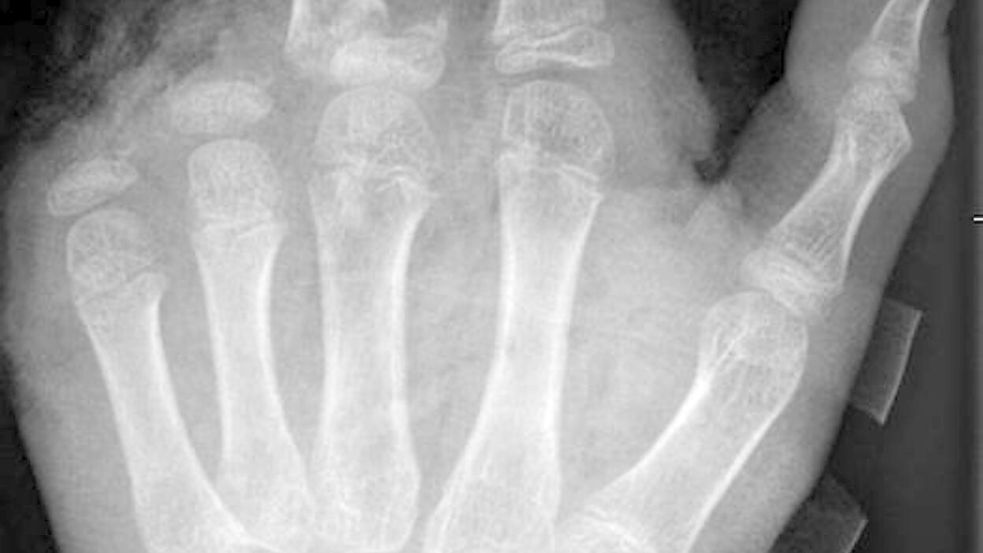

In der Handchirurgie müssten an Silvester im Unfallkrankenhaus rund 20 bis 40 Menschen mit Böllerverletzungen operiert werden, sagt die Ärztin. Dieses Jahr werde sie mir vier weiteren Handchirurgen im Einsatz sein. Die häufigsten Verletzungen entstünden durch explodierende Böller in der Hand.

„Der überwiegende Teil der Verletzungen trägt tatsächlich lebenslange Folgen mit sich, weil die Sprengkraft dazu führt, dass eben nicht nur einzelne Strukturen verletzt sind, sondern immer mehrere. Und das heilt praktisch nie ganz folgenlos ab.“ Zum Teil könnten Hände nicht mehr gerettet und müssten amputiert werden.